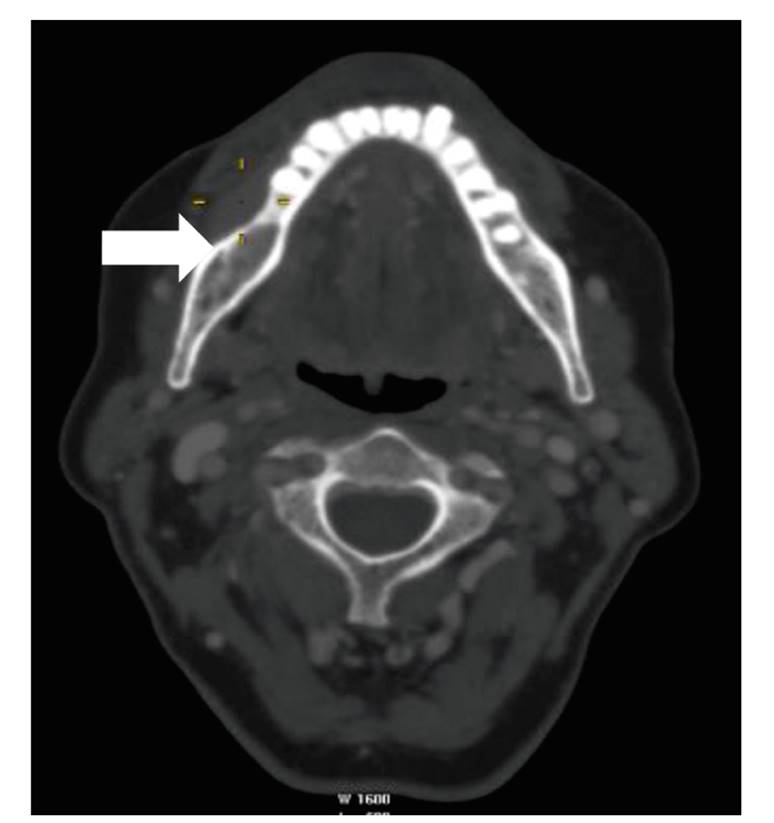

✅ Raíces que envuelven canal mandibular (visible en radiografía/TAC)

✅ Edad >25 años (raíces más formadas, hueso más denso)

✅ Extracción quirúrgica (vs. simple)

Nervios afectados:

• Nervio alveolar inferior (más común) → labio/mentón dormido

• Nervio lingual (menos común) → lengua dormida